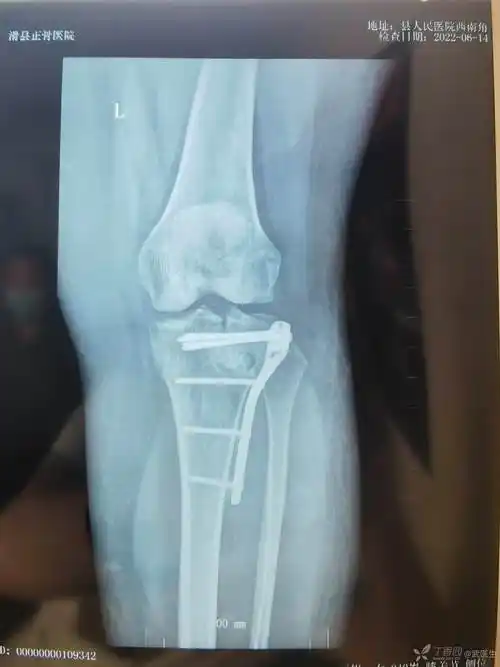

胫骨平台粉碎性骨折急会诊

复杂性胫骨平台骨折

一例复杂的胫骨平台骨折

复位不很完美的胫骨平台骨折

胫骨平台骨折的微创手术

胫骨平台骨折前外侧后外侧平台

胫骨平台骨折塌陷保守治疗